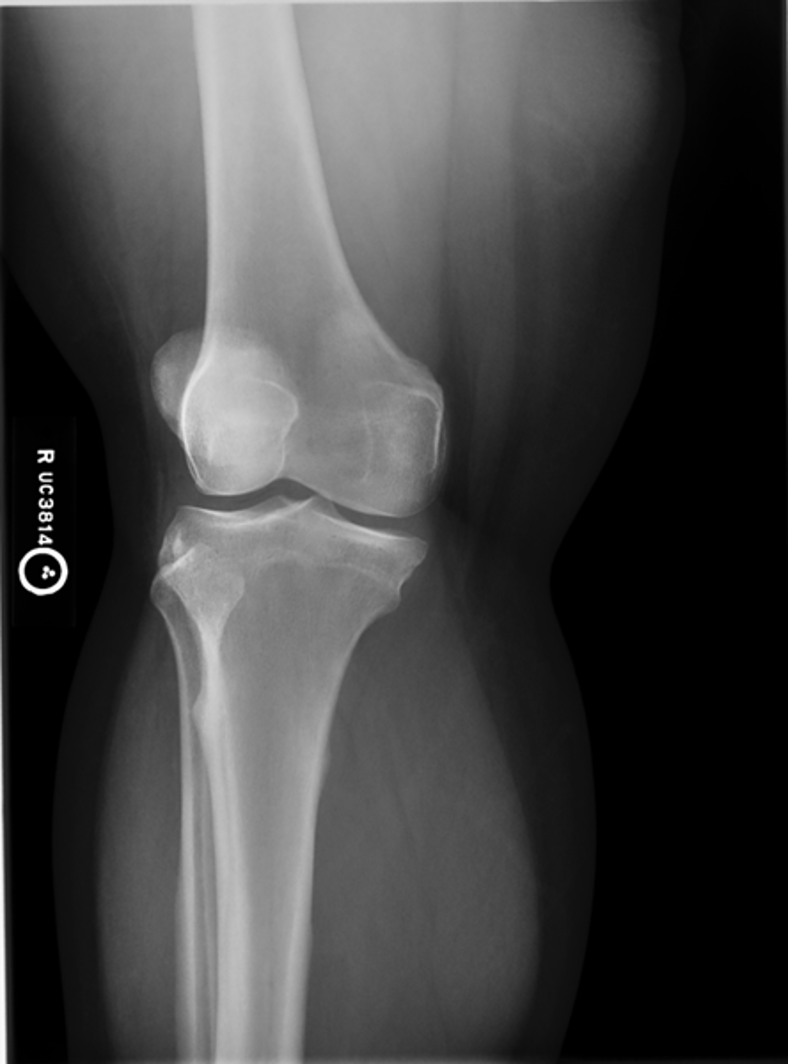

medial epicondyle

what is #1?

medial condyle

what is #2?

tibial plateau

what is #3?

tibial tuberosity

what is #4?

patella

what is #5?

lateral epicondyle

what is #6?

lateral condyle

what is #7?

intercondylar eminence

what is #8?

fibula

what is #9?

trochlear groove

what is labeled as the star?

intercondyle fossa

what is labeled as the check mark?